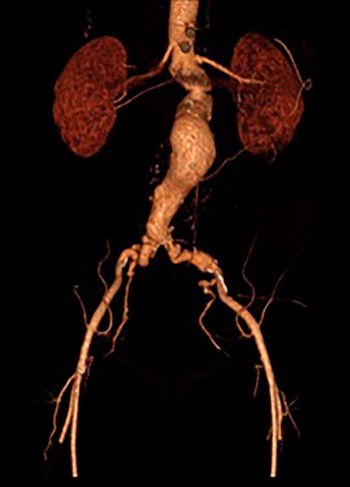

A 65-year-old man was admitted electively with a 55-mm infrarenal abdominal aortic aneurysm (AAA). Computed tomography (CT) angiography had demonstrated aneurysm morphology that was suitable for EVAR, although there were some adverse features with the neck (16 mm length, but conical and angulated) (Fig. 1). His past medical history was significant and included type 2 diabetes mellitus, obesity (body mass index of 32.2 kg/m2), hypercholesterolaemia, ischaemic heart disease (with coronary artery bypass graft) and associated moderate left ventricular systolic dysfunction, chronic obstructive pulmonary disease, arthritis and poor mobility requiring a wheelchair. Following discussion in the local multidisciplinary team meeting a decision was made to offer percutaneous EVAR under local anaesthesia.

Post-EVAR angiogram showing acute thrombosis of the right limb and subtotal thrombosis of the left limb and trunk.